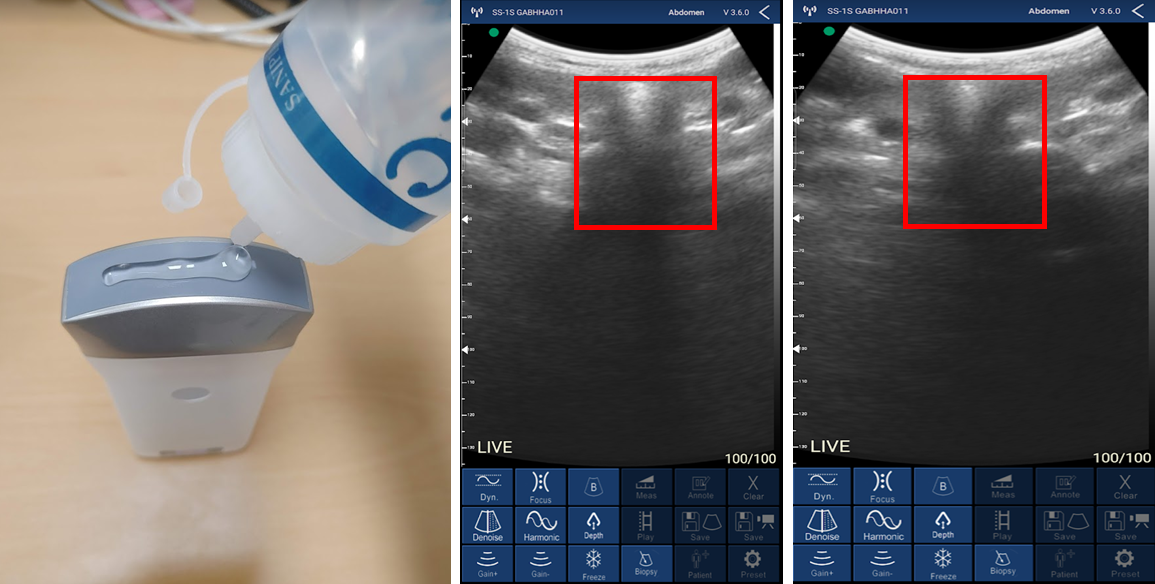

이제 갑상선을 봐야겠죠? 초음파에 젤을 바르고 갑상선 위치에 대어 봅니다. 휴대폰에 갑상선이 출력된 것을 확인할 수 있습니다.

그런데 인터넷 찾은 것과 비교하여 무언가 화질이 떨어지는거 같습니다. 지인 외과의사에게 초음파기를 주며 물어보았습니다. 인터뷰 결과 출력물을 육안으로 확인이 가능하나 화질이 떨어져 불편하다고 합니다.